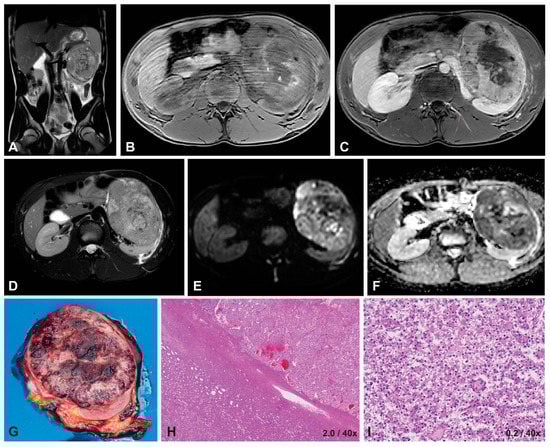

3.1. Case Presentation

3.1.3. Imaging Characteristics at Diagnosis

3.1.4. Diffusion-Weighted Imaging